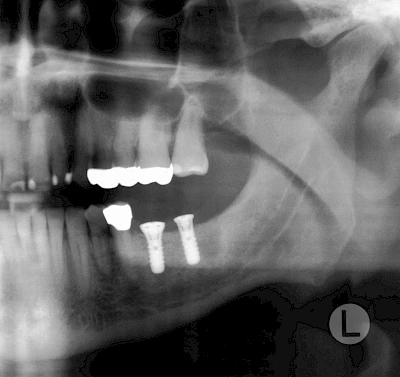

Nicht selten ist jedoch auch eine technisch aufwändigere Vermessung im Vorfeld sinnvoll, z. B.:

- Wenn sich der Kieferknochen abgebaut hat

- Wenn der Nervverlauf im Unterkiefer beachtet werden muss

- Wenn die Ausdehung der Kieferhöhle im Oberkiefer beachtet werden muss

- Wenn wenige Restzähne keine gute Orientierung erlauben

In diesen Fällen kann die Planung mittels verschieden aufwendiger Röntgen-Techniken (Übersichtsaufnahme, DVT) ggf. unter Zuhilfenahme speziell angefertigter Planungsschablonen sinnvoll sein.